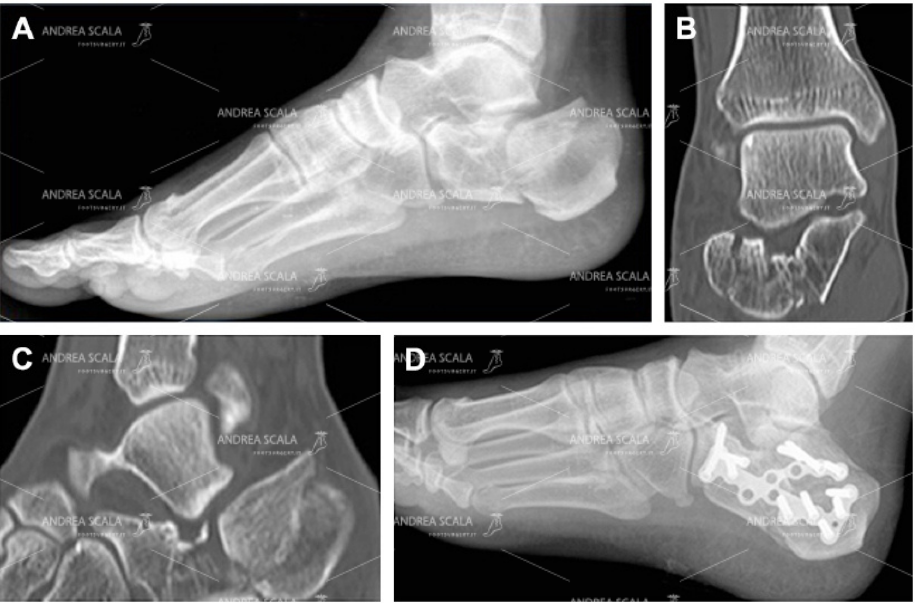

Non si spiega perché la maggior parte degli Ospedali non operano la frattura di calcagno con placca e viti. Gli Ospedali dovrebbero avere sempre qualche specialista particolarmente addetto alle fratture del calcagno. Viene utilizzata una operazione in cui perforano la pelle e infilano nel calcagno fratturato alcuni fili di acciaio (Kirschner). Ma i risultati sono scadenti perché i pezzi del calcagno non vengono rimessi a posto. I pazienti rimangono con il piede rotto come il giorno dell’incidente. Il paziente ha l’impressione di essere operato perché viene effettivamente ricoverato e portato in Sala Operatoria, ma la frattura difficilmente viene ricomposta.

La Radiografia mostra la frattura di calcagno curata con i fili di acciaio. Si vede molto bene che il calcagno è rimasto schiacciato. L’angolo di Bohler non è stato ripristinato, questo fa capire che l’articolazione non è stata ricostruita

La TAC eseguita dopo l’intervento con i fili di acciaio fa vedere molto bene che il calcagno è rimasto schiacciato. L’angolo di Bohler non è stato ricostruito. L’articolazione è rimasta infossata come il giorno dell’incidente.